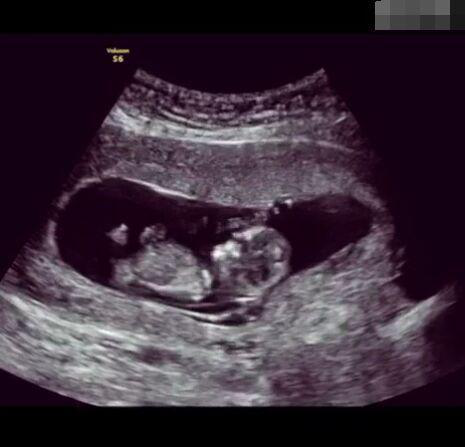

那些做了B超檢查確定胎兒男女,生下來后發(fā)現(xiàn)不對的,多半是因為在B超檢查時寶寶太調(diào)皮,以致影響了檢查準(zhǔn)確性。就比如說,有的女寶寶在媽媽肚子里玩自己的臍帶,把臍帶夾到了兩腿中間,B超就有一定幾率拍出來好像是男寶寶的特征,導(dǎo)致被誤認為是男孩子。還有些男寶寶過分害羞,在做B超時雙腿緊緊并攏,醫(yī)生也很難判斷男女,只好大致猜測是女孩,就又造成了誤會。因此,B超亦不是萬能的。